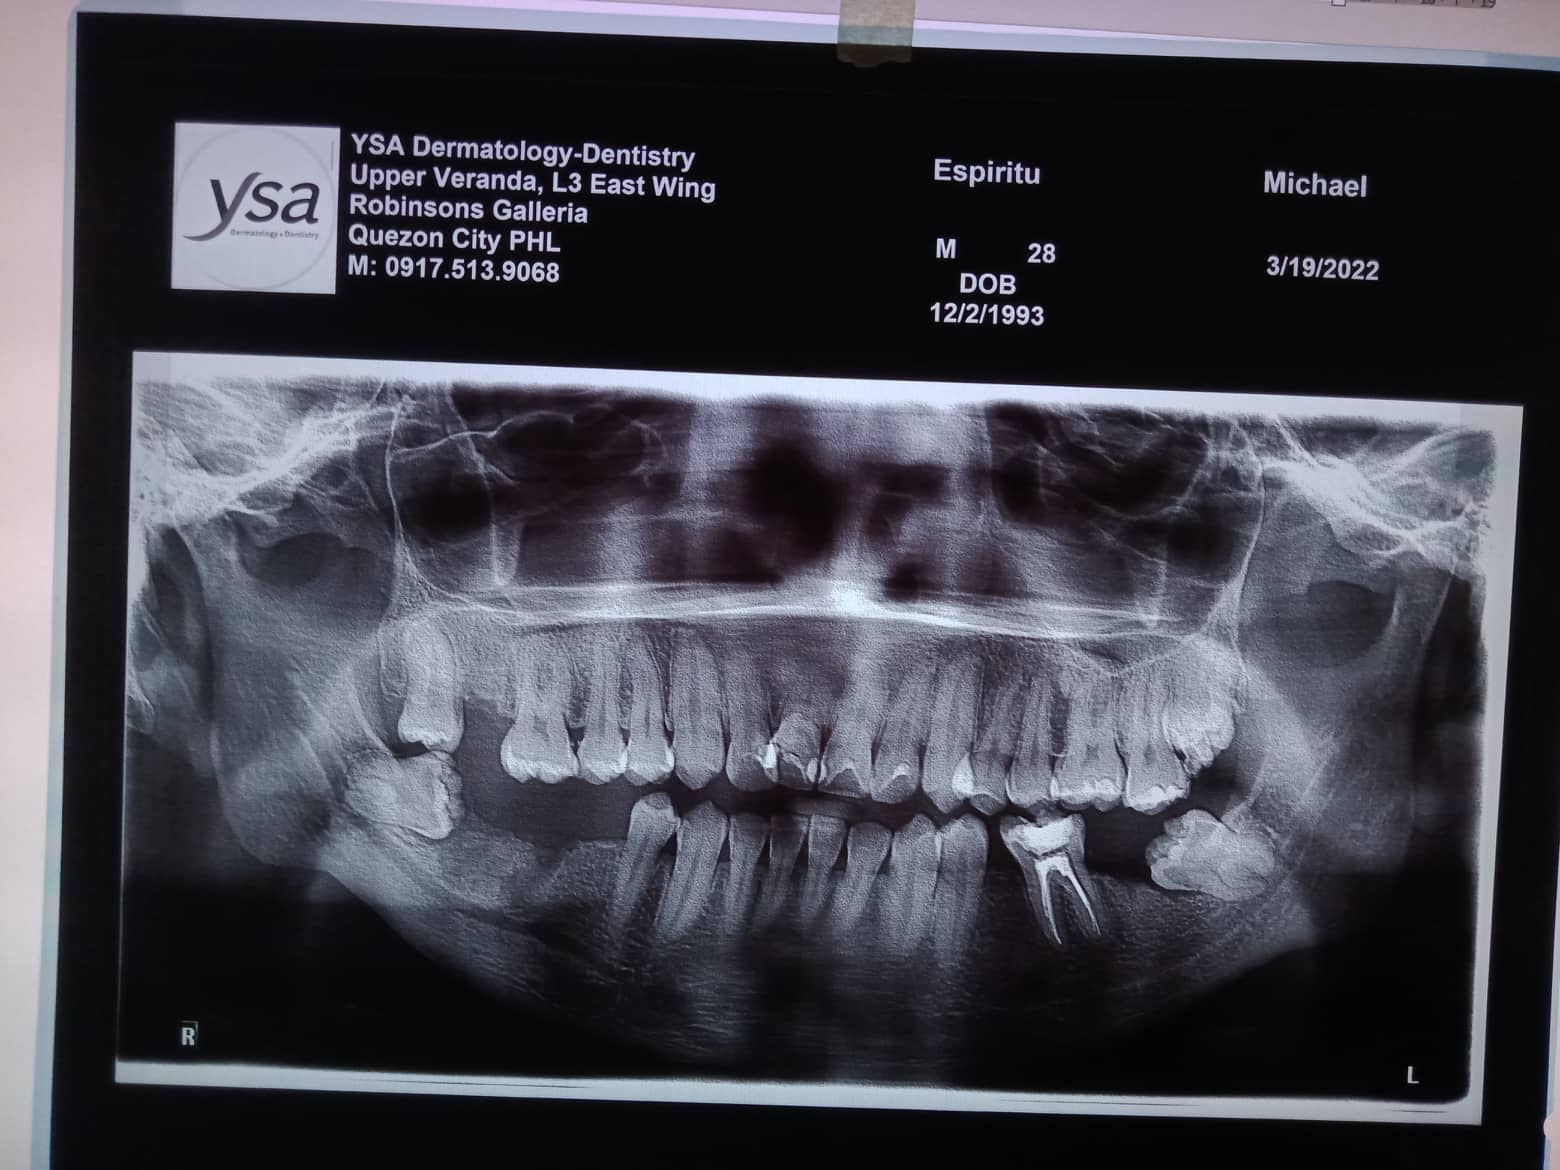

Edit Record Check our patient data records. Add patient information Patient Info Profile picture Last Name First Name Middle Name Birthdate Age Street Barangay City Country Zip Code Contact number Email Procedure 1/14/22- 12,22,36 - Xray LC # 26,27 & OP 1/29/22 - LC #12 - Mesial , lingual, labial LC#11 Surfaces mesial, distal, lingual, labial LC #21 - Mesial 2/19/22- exo 37 *for rct 4 canals 36 2/25/22 DB 21mm DL 22 mm MB 20.5mm ML 20mm formocresol with eugenol 2/05/22- camphenol/ white file *no sensitivity to hot and hold and during auscultation/ TF 2/12/22- no more pain. no more sensitivity/camphenol **next meeting xray. laser/ obturation 3/18/22- laser/ obturation/filling with fiber/ occlusal/ buccal/ lingual/mesial *observe 03/22/22- mbt 0.22/ 14 niti Ul/ class 3/ crowding ceph/ pano/ intraoral/ extra oral photos/ *** to ff up- cast analysis with ortho brush and wax 4/22/22- 14 niti UL RW #31 05/21/22 adj same wire/ req for ceph for exo Pm upper LR 7/2/22- Same wire 14 niti U/L RPI 22 Distal w/ RW Request Tad fot 4th Q 07/28/2022-U 0.016SS; placed ocs bet 11 and 13. L 0.016NITI; changed ligaties only. 08/27/22- SAME WIRE/ rpi 13/22 9/29/22 - RPI #21/#22, U 16ss wire, CHAIN #13-#15, INDIV #12-26; L SAME WIRE INDIV 11/04/22-ADJ/reattached 12/2/22- adj/1 reattached #36 01/13/23-adj 04/17/23- adj 16ss U indi/18 ss L chain 05/13/-23- U - same wire, individual/L - 16 ss, chain/Resto #11D class III 06/16/23- ortho UL same wire, U: individual L: chain RW # 31M 07/15/23- 18 ss U/ Rw 11M/ same wire lower chain lower closing space 08/15/23- closing space/ same wire ***for Lc 14/15/16 09/19/23- same wire/ chain upper/ chain 32-35 chain 11/12/24- ipr 11/21 DISTAL/ CLASS II ELASTIC chipmunk for TADS - 3500 01/27/24- same wire chain upper reattached # 02/28/24 -same wire -reattach #14 03/27/24 16x22 lower chain U RW #42 mesial for removal for the month of june 04/27/24 #14 reattached- no charge same wire chain U/ chain #33-34 05/28/24 16x22 U/L chain 32,34 class II elastic one quadrant II to III chipmunk 06/28/24 removal of brace File 300986490_754411172436439_2707532318128906720_n.jpg File 2 299958020_854700088834251_2016017323265959674_n.jpg File 3 302089664_596777748599375_6189577205987709592_n.jpg File 4 302471710_409703067737285_7864073801397539615_n.jpg File 5 302092198_453164560086776_1373823481126109582_n.jpg File 6 espiritu.jpg File 7 michael_espiritu.jpg File 8 michael_espiritu_1.jpg File 9 File 10 File 11 File 12 File 13 File 14 File 15 File 16 File 17 File 18 File 19 File 20 Retain Record Retain Record Yes No Save Your Changes